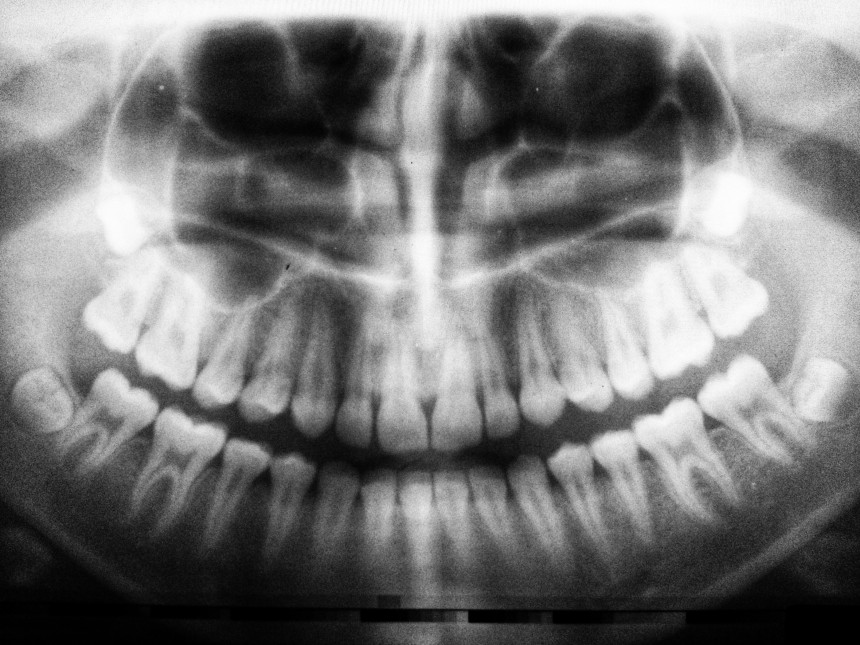

Zāles, kas spēs cilvēkam izaudzēt jaunus zobus, būšot gatavas jau pēc pieciem gadiem

Mēs visi zinām, ka kauli sadzīst, bet zobi neatjaunojas. Bet, iespējams, tas tā vairs nebūs ilgu laiku - zinātnieki no Japānas ir veikuši revolucionāru atklājumu, kas varētu mainīt zobārstniecības principus, raksta “postimees.ee”.

Lai gan kauli pēc lūzuma var paši sadzīt, zobi to nespēj, tāpēc miljoniem cilvēku visā pasaulē cieš no edentulisma jeb zobu trūkuma. Tagad japāņu zinātnieki sāk daudzsološus zāļu, kas stimulē zobu ataugšanu, izmēģinājumus ar cilvēkiem. Ja izmēģinājumi būs veiksmīgi, pētnieki cer, ka zāles būs pieejamas visu veidu zobu trūkuma ārstēšanai aptuveni 2030. gadā.